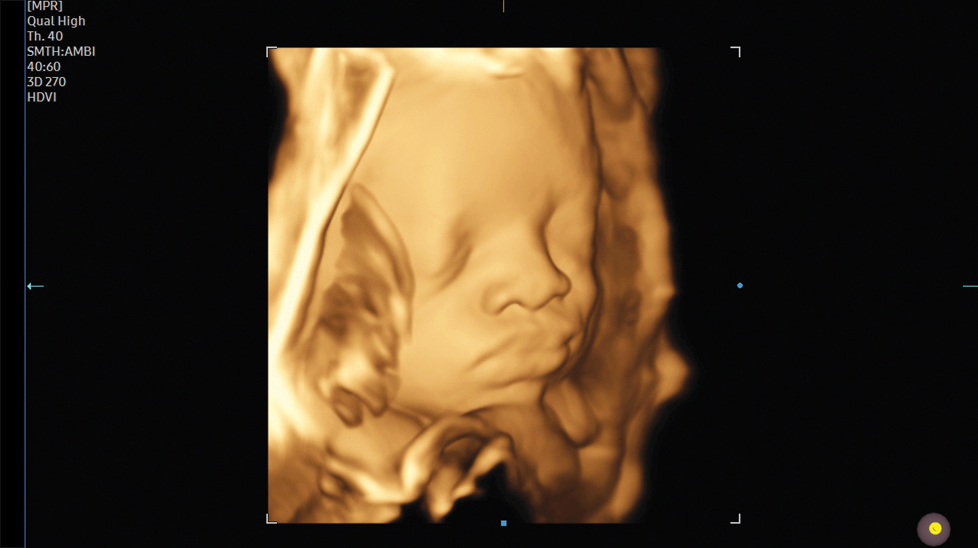

Реалистичное описание характеристик 3D / 4D

CrystalLiveTM в формате 3D / 4D обеспечивает пользователям более реалистичные изображения с высоким разрешением. Она превосходит традиционные технологии 3D-визуализации в плане просмотра мелких деталей и световых эффектов.

Реалистичное отображение 3D-анатомии RealisticVue™ отображает 3D-анатомию в высоком разрешении с исключительной детализацией и реалистичным восприятием глубины. Выбираемое пользователем направление источника света создает затейливо градуированные тени для более четких анатомических структур.TM

на изображении: Ранний зародыш с помощью RealisticVueTM

Объемное изображение высокой четкости HDVITM - это технология объемной визуализации, которая улучшает визуализацию краев и небольших структур на объемных данных. Улучшенная выразительность границ и насыщенность изображения позволяют передать самые детали от угла до тени плода.

на изображении: Позвоночник плода с 3D